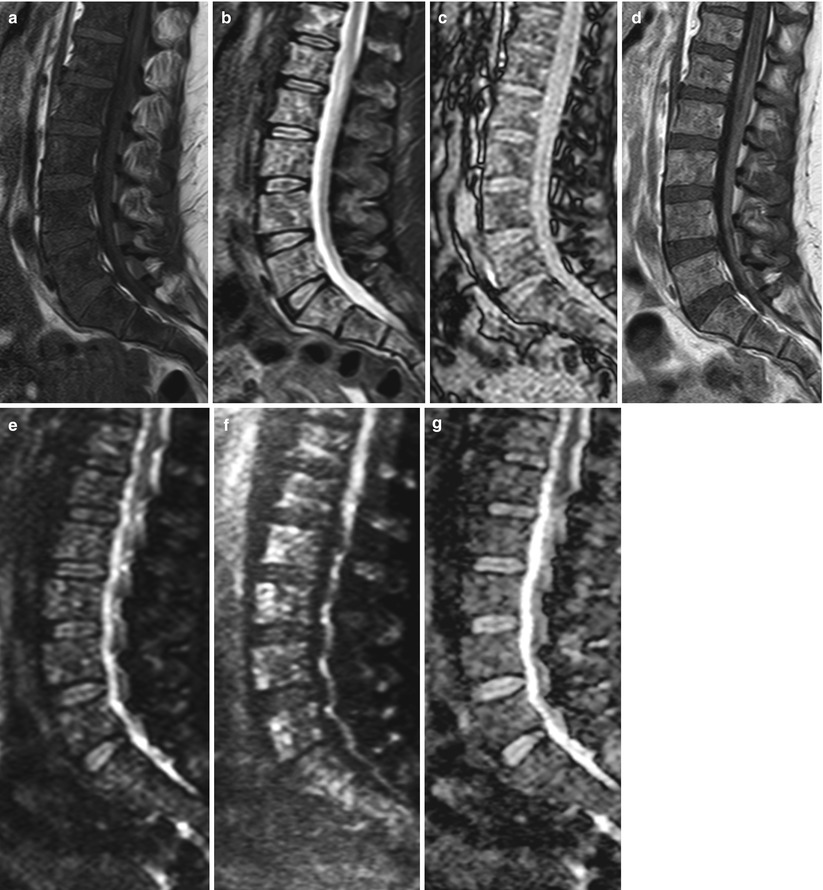

Get Causes Of Abnormal Bone Marrow Signal On Mri PNG. (c) resolution of the hyperintense signal on a posttreatment. When an mri shows abnormal bone marrow signals in the hip, there could be a number of causes.

Myeloproliferative these encompass a broad category of diseases caused by abnormal growth of hematopoietic marrow elements, such as. Bone marrow cancer happens when cells in the marrow begin to grow abnormally or at an accelerated leukemia usually involves white blood cells. Incidentally noted abnormal or heterogeneous bone marrow signal on mri was not inconsequential.

White blood cells fight off infections that enter the body. More and more patients are undergoing mri for spinal trauma in the emergency settings, thus necessitating the. Bone marrow cancer is a broad category that includes many types and treatment options. This ppt is about interpretation of bone marrow signal changes in mri.